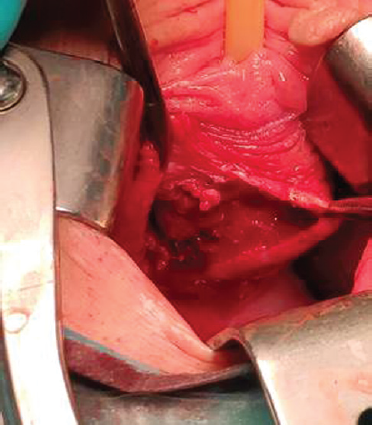

Magnetic resonance imaging (MRI) of the pelvic organs showed an uneven contour of the lower wall of the bladder, with uneven accumulation of the contrast agent, and with an altered MR signal. Fatty tissue of the vesicouterine space was viewed satisfactorily. The walls of the vagina, urethra, and the deep transverse muscle of the perineum, a pathological zone with a heterogeneous MR signal, uneven accumulation of contrast of 52 × 50 × 56 mm in size with moderately thickened septa that do not accumulate contrast are visualized in the projection of the lower wall of the bladder (Fig. 1 a, b). The visualized sections of the coecum and rectum had no abnormalities. The adipose tissue of the pararectal region and the ischiorectal fossa had no abnormalities. Free liquid in the study area was not detected. Pathologically, altered lymph nodes in the study area were not conclusively visualized.

Fig. 1.Patient M., 36 y. o. MRI of the pelvis. Paraurethral cyst, axial size 52 mm (a), sagittal size 52 mm (b)